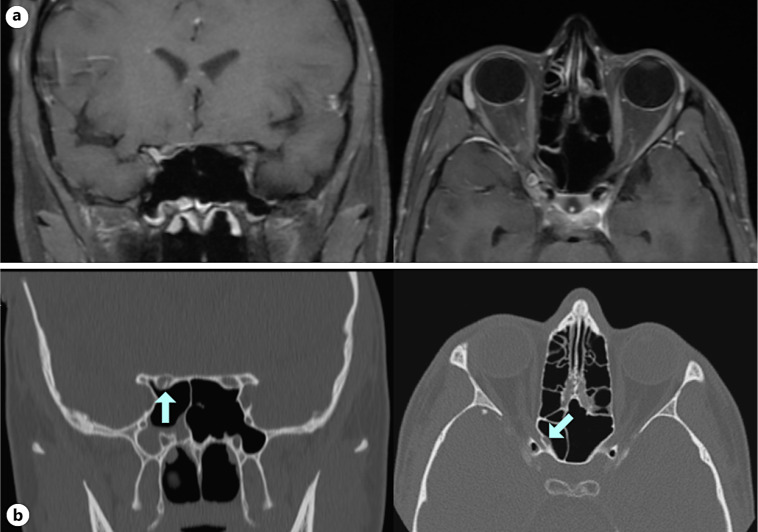

Case presentation: A 19-year old male presented with immediate total loss of vision to no light perception in the right eye after being struck on the left cheek by a lawn sign. Computed tomography and magnetic resonance imaging revealed left orbital floor fracture and right optic nerve enhancement. The patient was treated with high-dose intravenous corticosteroids and plasma exchange for a presumed inflammatory or TON. Repeat orbital imaging revealed a right OCF with bony impingement of the optic nerve. The patient underwent endoscopic optic nerve decompression; a 4 × 5 mm bone fragment abutting the optic nerve was removed. 1 month later, vision improved to hand motion.